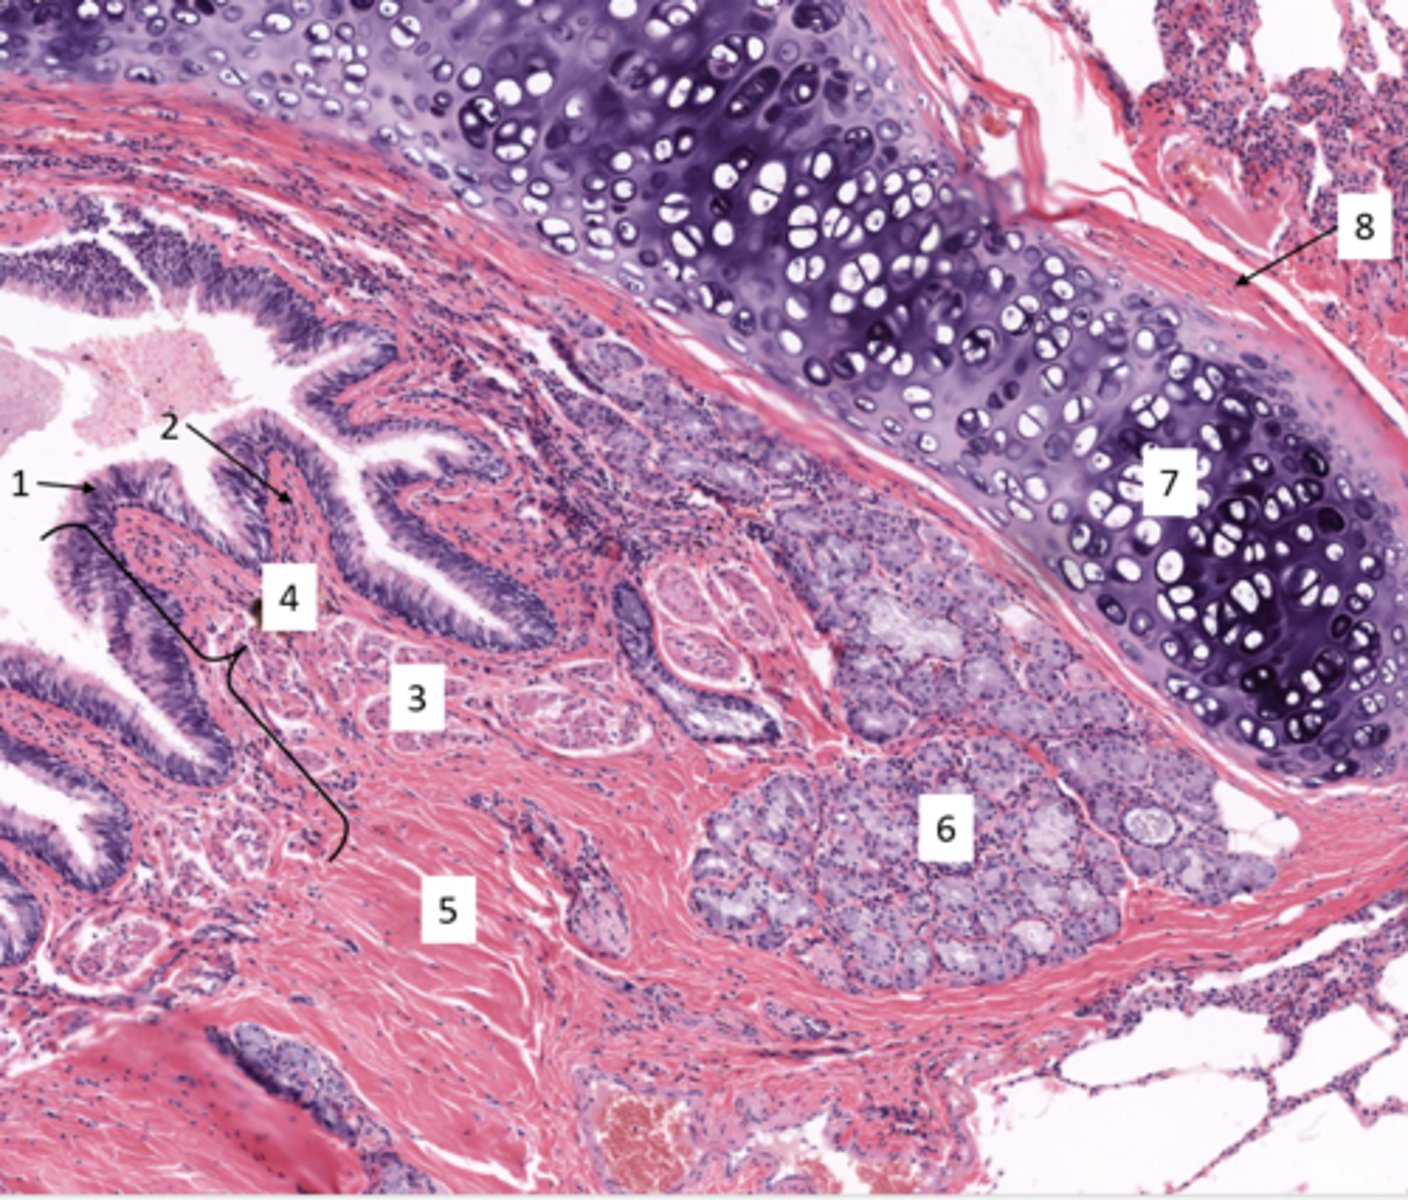

Identify the type of airway

bronchi

These glands are in which layer of the trachea?

submucosa

Identify the gland in the mucosa and submucosa

seromucous gland

Identify the cell at 5

mucous cells

Identify the cell at 4

serous cells

Identify this type of airway

bronchioles

Identify the type of bronchiole

terminal bronchioles

respiratory bronchioles

Identify the airway segment between the lines.

alveolar ducts